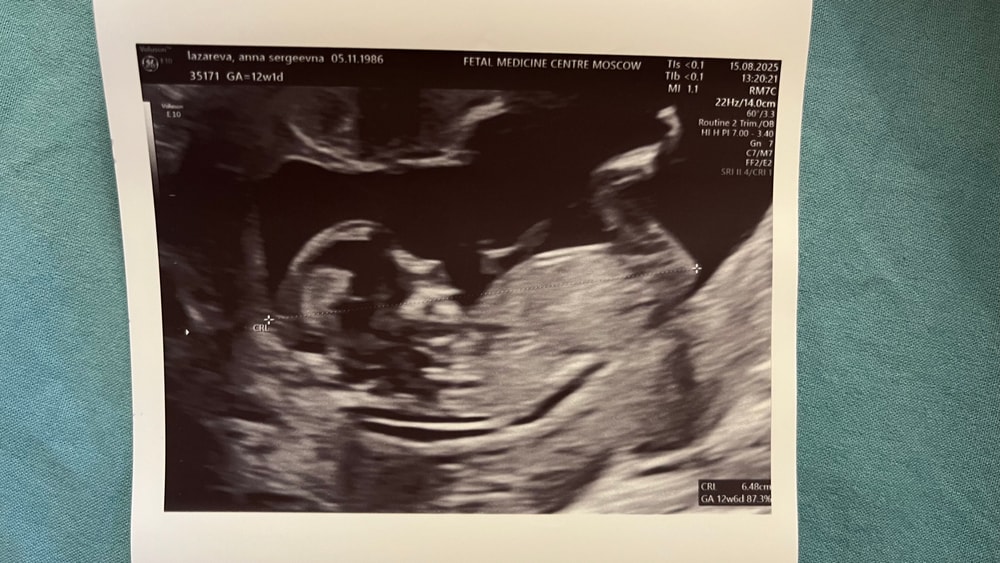

Делали платно в Центре медицины плода на Чистых прудах у Батаевой Р.С. Врач понравилась. Показалось, что у неё черный пояс по узи, так она быстро и четко всё делала, я в шоке 😅 Сказала, что у нас всё хорошо (тьфу-тьфу 🤞🏻).